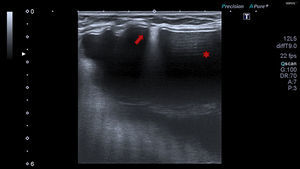

Caso clínico 1Mujer de 49 años con historia de melanoma dorsal izquierdo en estadio IA de la AJCC en el año 2006. En enero de 2014 la paciente refería palparse un bulto en la axila izquierda. A la exploración se trataba de una lesión nodular subcutánea de aproximadamente 2cm, de tacto firme, no adherida a planos subyacentes. Con la sospecha de adenopatía metastásica se remitió al servicio de radiodiagnóstico para realizar una ecografía. En la ecografía (Toshiba Aplio 500, sonda lineal multifrecuencia 7-11MHz) se visualizó una imagen hiperecogénica difusa con mala transmisión sonora, de 2cm de diámetro mayor, localizada en el tejido subcutáneo (fig. 1A). Esta imagen ecográfica se ha descrito como en «tormenta de nieve», y es altamente sugestiva de siliconoma por rotura de prótesis mamaria. Tal es así que en el mismo acto se realizó una ecografía mamaria, apreciándose gel extravasado al espacio comprendido entre el pliegue de la cubierta externa de la prótesis y la cápsula externa fibrótica, hallazgo que confirmó la rotura capsular de la prótesis mamaria izquierda (fig. 2). En la anamnesis la paciente confirmó haberse implantado unas prótesis Poly Implant Protheses (PIP) en el año 2008.

A. Imagen hiperecogénica localizada en tejido celular subcutáneo, de morfología arriñonada, ecoestructura homogénea de límite superior y laterales nítidos y pérdida de borde profundo por artefacto en tormenta de nieve. B. Dos imágenes hiperecogénicas adyacentes pseudoencapsuladas en «tormenta de nieve» en tejido subcutáneo. Ausencia de vascularización con doppler color.